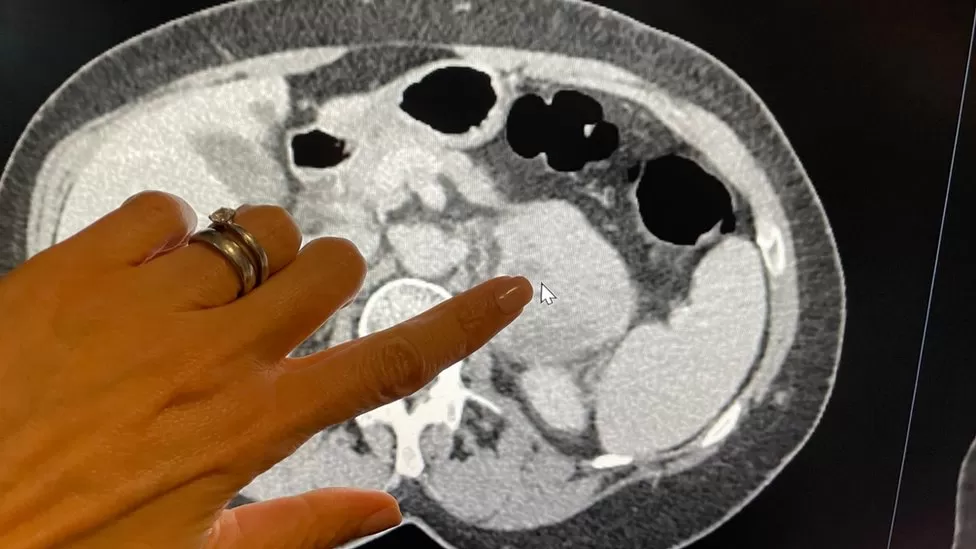

When dental nurse Tina McLaughlan was diagnosed – in June last year, after stomach pain – with a sarcoma at the back of her abdomen, doctors relied on computerised-tomography (CT) scan images to find the problem.

They decided it was too risky to give her a needle biopsy. The 65-year-old, from Bedfordshire, had the tumour removed and now returns to the Royal Marsden for scans every three months.